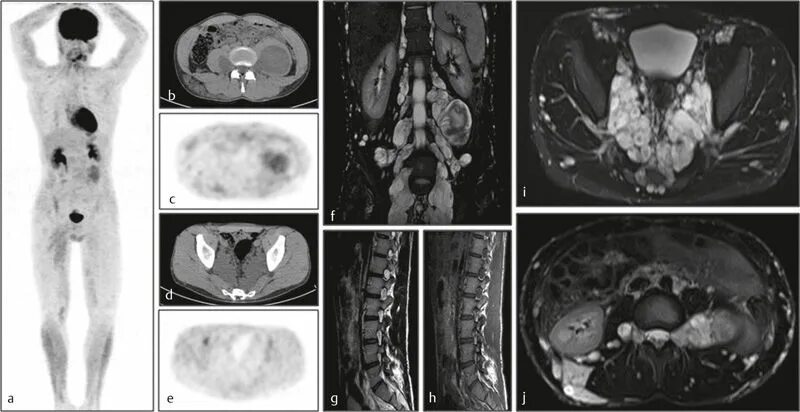

Нейрофиброматоз мрт